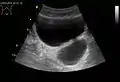

• Urethral diverticula are usually found in women aged 30 to 70 years old, in between 1 and 6% of adult women. Since most cases are without any symptoms, the true incidence is unknown. Symptoms may vary from frequent urinary tract infections, painful sexual intercourse (dyspareunia), or symptoms due to cancer. A urethral diverticulum is located on the anterior vaginal wall, 1 to 3 cm inside the vaginal introitus. MRI is preferred as the imaging method of choice due to its excellent soft-tissue resolution. On T2-weighted imaging, it shows a high signal in the diverticulum due to the presence of fluid inside it. Vaginal ultrasonography is highly sensitive in diagnosing the diverticulum, but it is strongly dependent on the skills of the operator.[15]